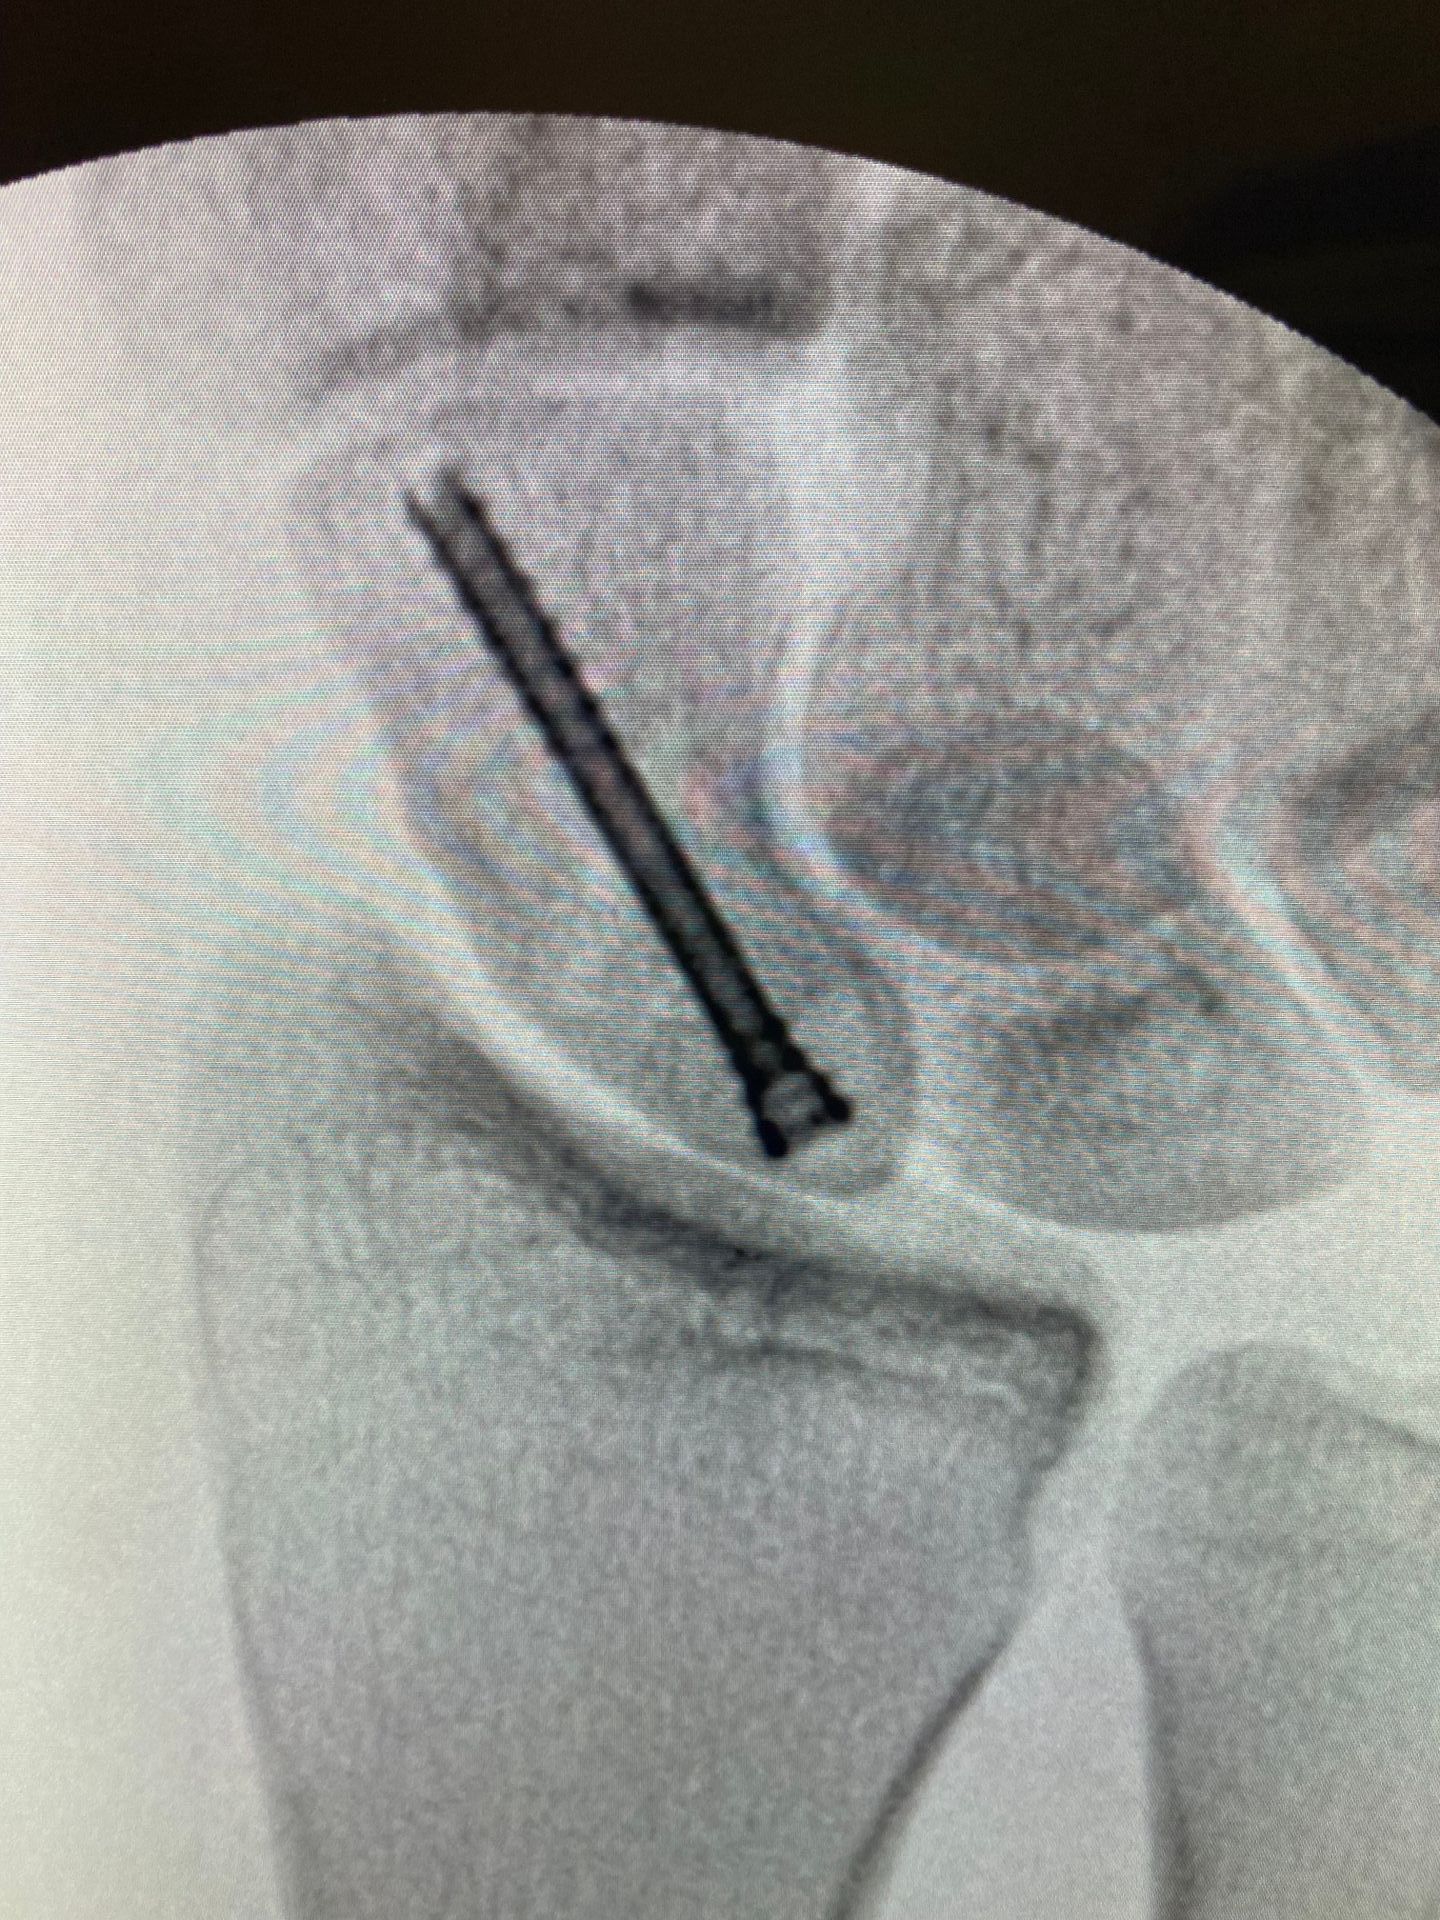

- De modo geral, o tratamento da fratura de escafóide será feito através do uso de um parafuso canulado inserido através de uma pequena incisão. Esse acesso pode ser na palma da mão ou no dorso do punho.

- Herbert e Fisher, em 1984, apresentaram os resultados de 158 pacientes operados com um parafuso de características diferentes dos demais, revolucionando o tratamento de escafóide. Esse tipo de parafuso apresenta passo de rosca da porção anterior do parafuso diferente do da porção posterior, possibilitando compressão da fratura

- Durante o ato cirúrgico, o cirurgião de mão utilizará um equipamento chamado radioscopia para guiar a introdução do fio guia e do parafuso. Através desse equipamento e de referências anatômicas, será definida a posição ideal do parafuso. Por exemplo, no plano coronal, um bom parâmetro radiográfico da posição distal do parafuso é o ⅓ da distância do lado radial do pólo distal do escafóide